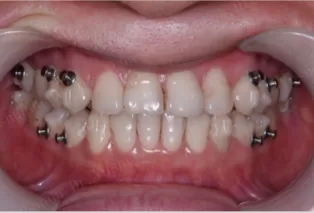

Photos intra-orales